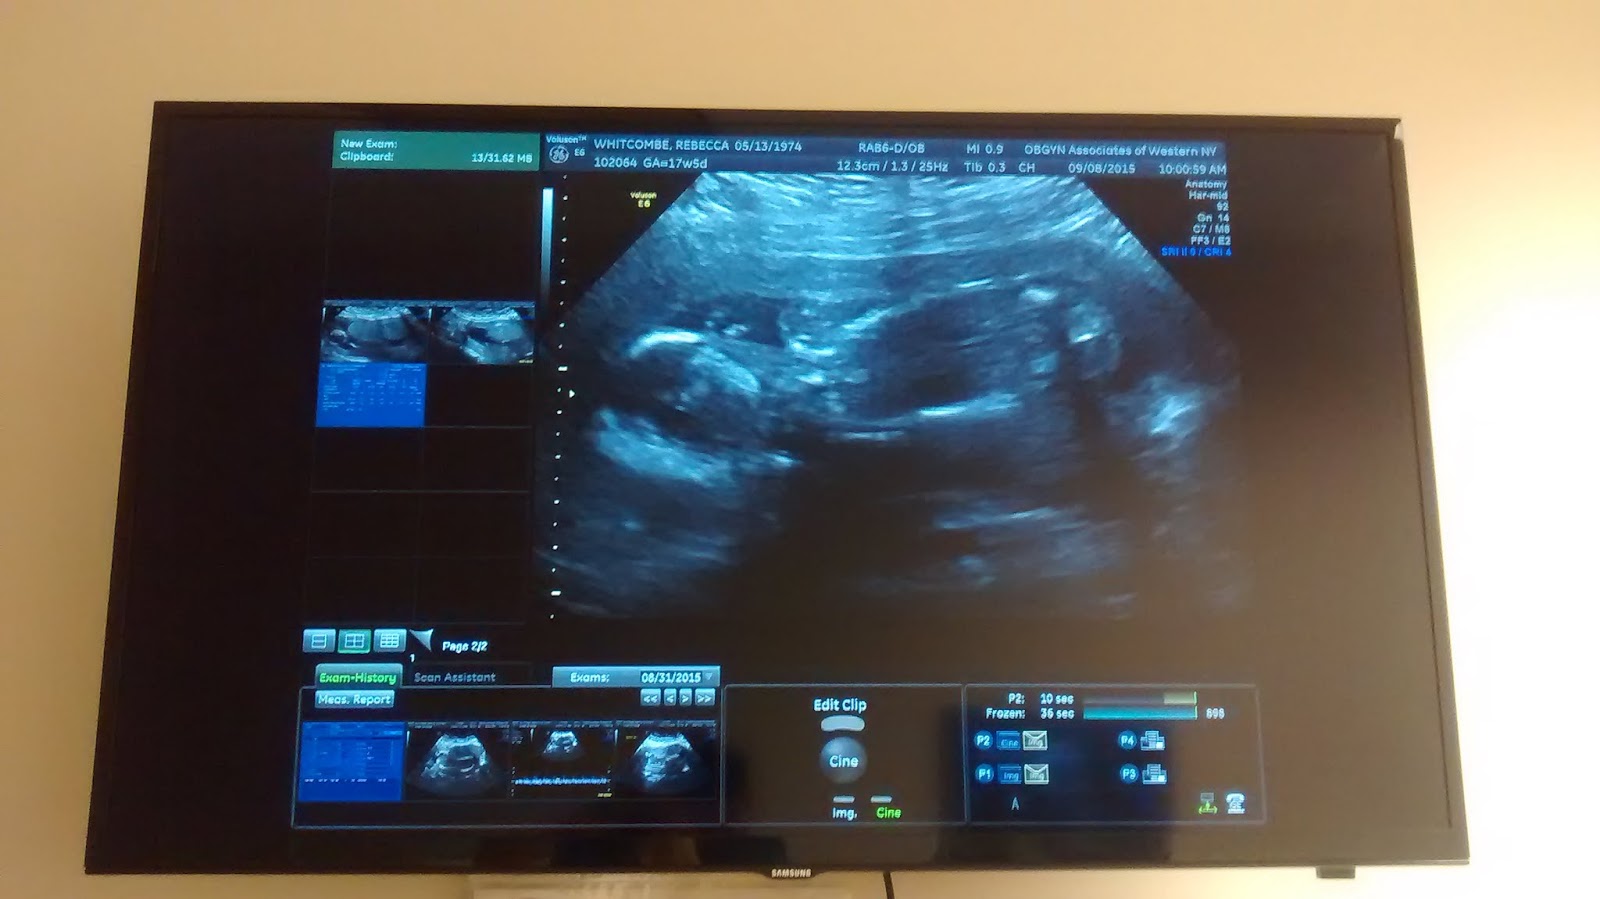

But the baby is getting bigger....physically is perfect and has a strong heartbeat. So far so good. I've had more sonograms with this one than the other 2 combined. Maybe this on likes the attention?

This was today and the fluid was still a bit low and was before the doctor stated we will keep watch and see.